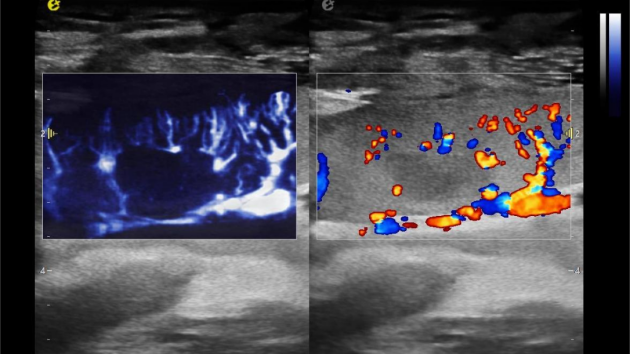

1) 实时查看血管吻合情况,确保新肾"通电"后动、静脉血流是否畅通;

2) 监测肾门处血流频谱及时干预血栓的形成,减少术后血管并发症的发生率;

3) 观察肾皮质的血流灌注情况,评估肾移植的成功率。

1) 基于OmniSound?平面波超快速平台,超声信号采集帧频提高了200倍(25000Hz)。

2) 可检测20-50μm级细小血管低速血流信号,能看清头发丝1/2粗细的微血管;

3) 通过血管指数(VI)定量评估局部血管密度,以定量化数据实时监测血流灌注情况,预判肾功能恢复情况;

超微视血流显像评估肾移植术后灌注情况